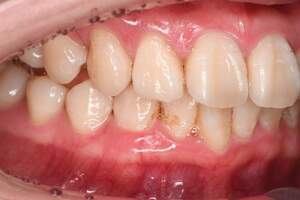

治療前

治療後

| 年齢 | 36歳・男性 |

| 主訴 | 歯石をとりたい |

| 治療内容 | 歯石除去 |

| 治療期間 | 30分 |

| 費用 | 約2,000円 |

| リスク・副作用 | ・歯ぐきの炎症が強いと歯石を取る際に出血することがあります。 ・処置後に歯がしみることがあります。 ・歯と歯の間に隙間ができるので、息が漏れ発音しにくいと感じることがあります。 ・歯ぐきの炎症が軽減すると歯ぐきが引き締まり、歯が長く見えることがあります。 |